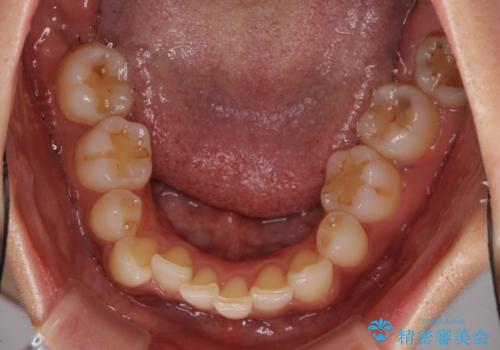

- 以前矯正治療をされていましたが、後戻りが起きたことを気にして来院された患者様です。

全顎的に認められた叢生を改善するため、インビザラインにて治療を行うこととしました。

前歯の叢生の改善を目的として、IPR(歯と歯の間を削る)と歯列全体の後方移動によって歯並びを整えることとしました。